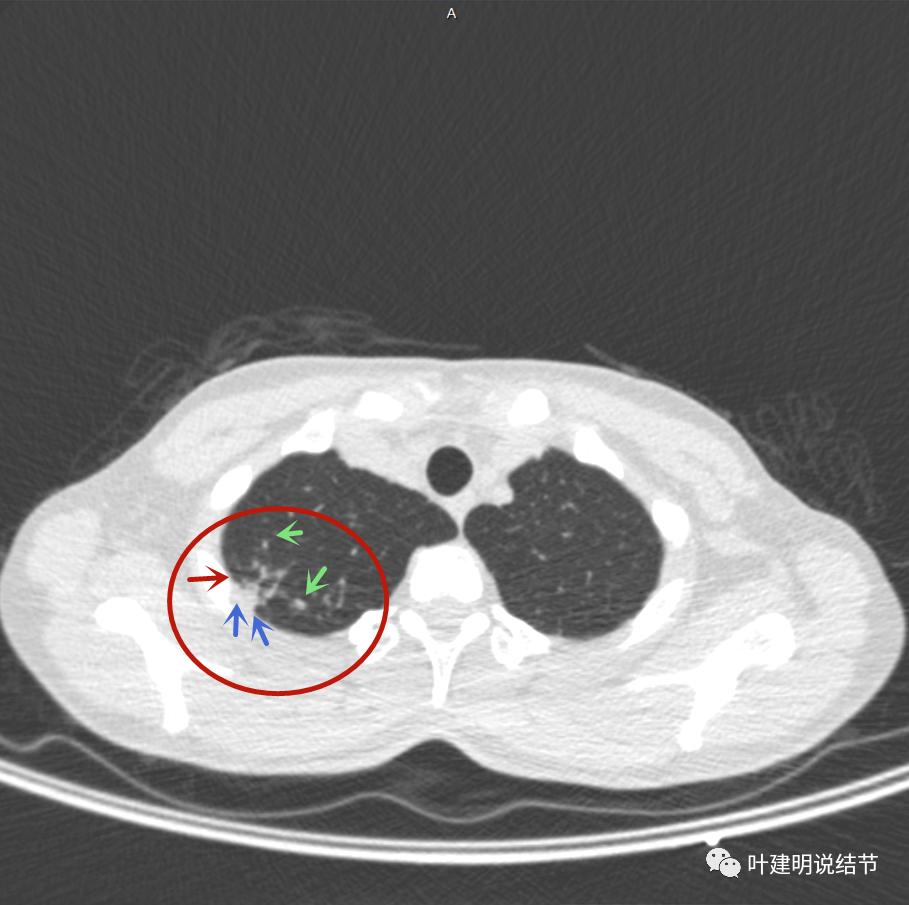

邻近胸膜明显增厚,且广基底,主病灶前方有小片磨玻璃影

主病灶与胸膜间基本相连,模糊清(蓝色箭头),主病灶壁厚薄欠均,边上有高密度条索状(桔色箭头)